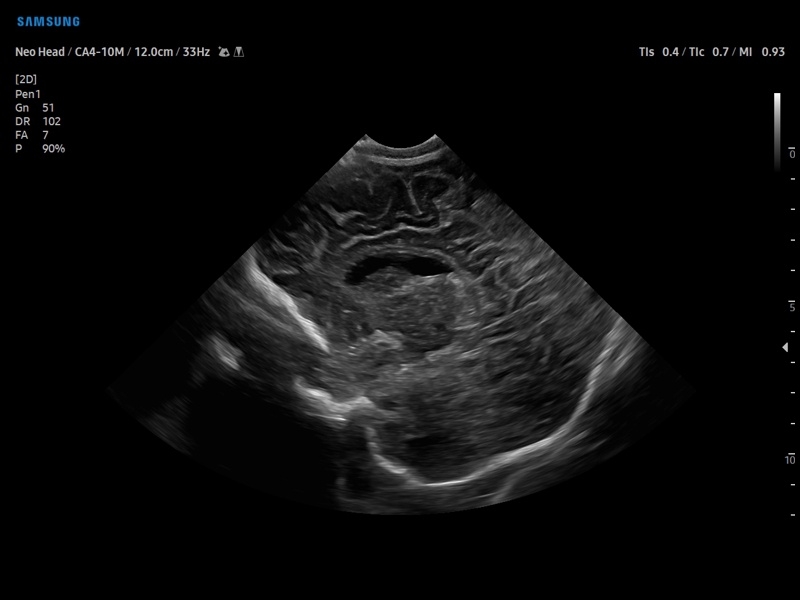

• Педиатрия и неонатология

• Модуль5D CNS– программа автоматического построения основных срезов головного мозга плода в режиме объемного сканирования.

• MSV(Multi-Slice View илимультислайсинг) - возможность одновременного просмотра на экране множественных срезов, полученных при трехмерном сканировании.

• VolumeCT - трехмерная реконструкция изображений в виде куба (Cube Sectional View) или трех пересекающихся плоскостей (Cross View).